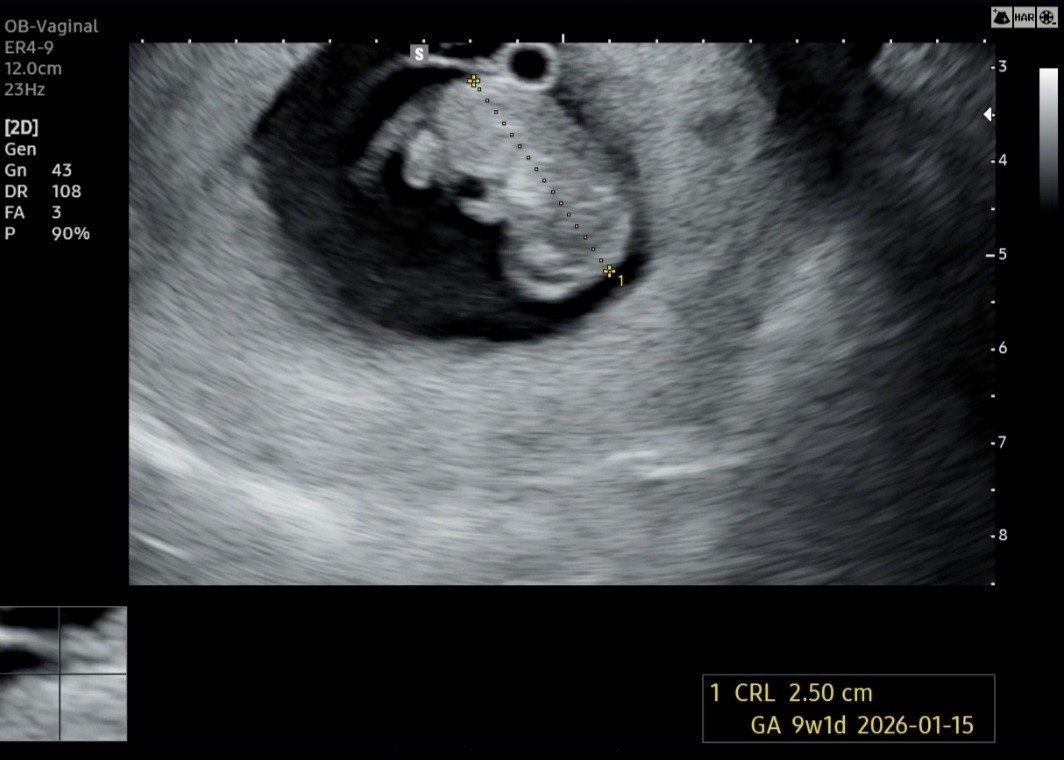

9주3일차에요 (젤리ㅎㅎ)

너무 귀여워요 근데 저 발밑에 긴거는 뭘까요? 궁금해요

탯줄 아닐까요~?